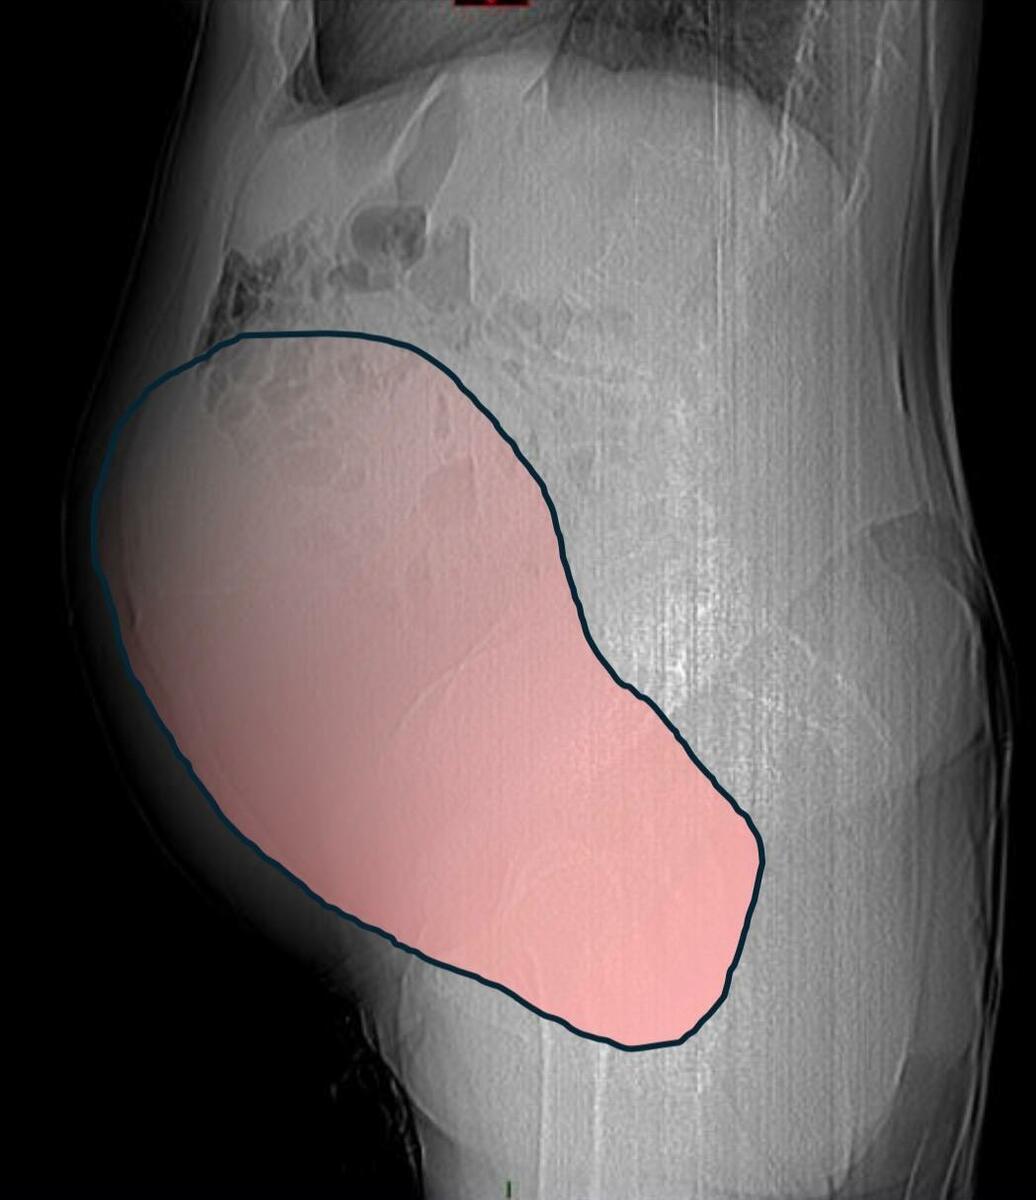

Per mesi la gigantesca cisti ovarica, con un diametro di circa 28 centimetri, è rimasta nascosta, senza dare segnali evidenti. La paziente non si era accorta di nulla. L’allarme è scattato quando la massa, associata alla presenza di una seconda neoplasia intestinale, ha iniziato a comprimere il colon, provocando sintomi acuti ed improvvisi fino a una grave difficoltà intestinale non più ignorabile.

Durante l’intervento emerge tutta la gravità della situazione. La gigantesca neoplasia ovarica viene asportata: pesa circa 6 chilogrammi, con un volume paragonabile a quello di una gravidanza gemellare a termine. Ma non è l’unica minaccia. I sintomi più pericolosi sono legati alla sofferenza intestinale, che richiede un intervento immediato e coordinato di più specialisti.